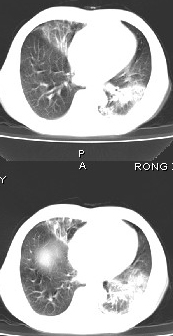

男68岁,反复发热、咳嗽,咯痰1月,曾有咯血史,双肺闻及呼吸音增粗。

左肺上叶尖后段及下叶多发实变阴影,内见支气管充气征,段以上支气管尚通畅,肺门区未见软组织肿块影,结合病人有反复发热病史,首先考虑感染性病变(干酪性肺炎不能排除),建议抗炎治疗后复查或结合纤支镜检查。

左肺上叶尖段及下叶干酪性肺炎可能性大,建议结合临床相关检查.右肺中叶炎症.建议治疗后复查.

该患者在25天前外圆平片见右肺中上肺野大片状影,(治疗不祥,在反复问病史后患者告诉;近一月住在新房内,搞装修),我认为首先考虑是感染,而且过敏性肺炎可能性大。

结果是过敏性肺炎,谢谢,楼主!